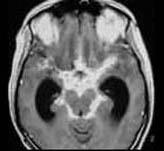

问题 女患者,35岁,发热、头痛、呕吐3天,体重减轻,有肺结核史5年。查体颈抵抗感,克氏征(±)头颅MRI表现如图,最可能的诊断是 ( )

选项 A、结核性脑膜炎 B、神经系统钩端螺旋体病 C、隐球菌性脑膜炎 D、单纯疱疹病毒性脑炎 E、病毒性脑膜炎 一、单项选择题

答案 A